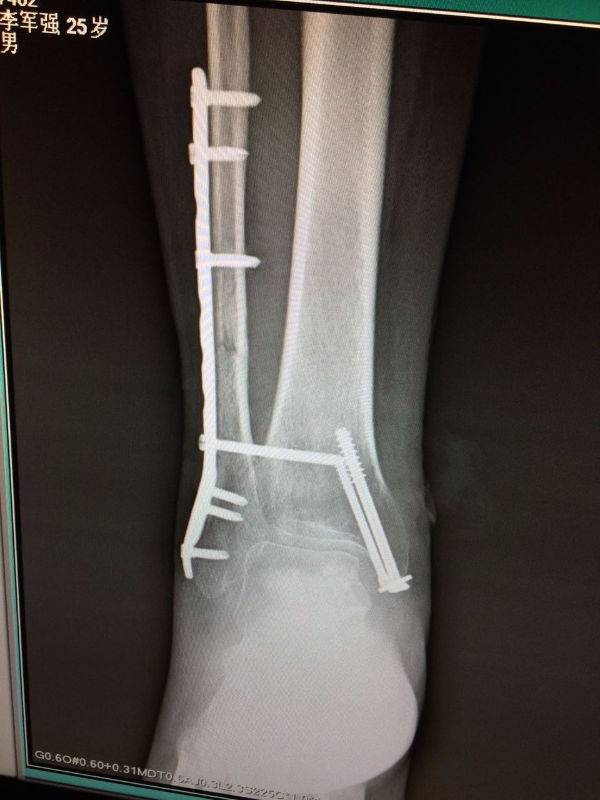

手术非常好,顺便请教一下。患者.男,25岁,右腓骨下段及内踝骨折,切开复位内固定术后120天,外踝部钢板外露,半月前行扩创缝合,目前仍未完全愈合,伴少量渗出,踝关节功能僵硬。请教治疗方案。谢谢

mmexport1496478281296.jpg